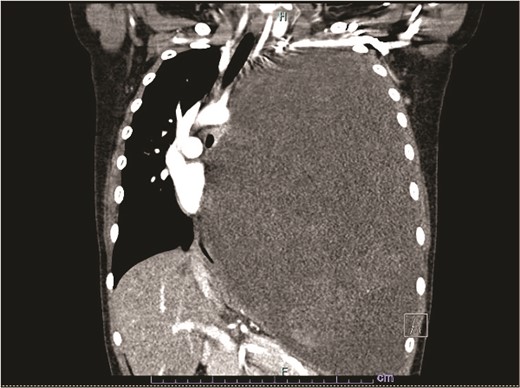

Our patient is a 10-year-old Caucasian female with a history of early adrenarche, ADHD, and COVID-19 and no past surgical history. She presented to the ED with a month-long history of persistent coughing, shortness of breath on exertion and speaking, and left-sided chest pain that began after a diagnosis of mildly symptomatic COVID-19. A physical exam revealed decreased breath sounds on the left, with a left-sided chest protrusion. A plain film and CT demonstrated a normal right lung, with a significant mediastinal shift toward the right, displacement of the heart into the right hemithorax, with complete whiteout of the left hemithorax, and demonstrating a mix of solid and cystic foci, with a round opacification at the left lung base (Figs 1 and 2). The patient underwent an uncomplicated left thoracotomy with excision of two masses, one being 22.5 × 21.0 × 10.5 cm and the other being 13.5 × 11.5 × 6.2 cm. These masses weighed 2394 g in aggregate. The specimens consisted of well-encapsulated tumors attached to the posterior aspect of the chest wall. A regional, positive lymph node measuring 3.0 × 2.2 × 1.0 cm was also resected. Due to the large size of the tumor and the requirement for clean margins, parts of the latissimus dorsi and serratus anterior muscles were also resected. By postoperative day (POD) 0, the left lung had already filled the left hemithorax, and the mediastinal shift had corrected (Fig. 3). The chest tube was removed on POD 5, and a plain film showed continued expansion of the lung to full size and resolving pulmonary edema and atelectasis (Fig. 4). The patient was discharged home on POD 5. The tumor staging was T4N1M0. The tumor was positive for vimentin, CD56, synaptophysin, chromogranin, and NSE. The tumor was negative for pancytokeratin, Cam5.2, EMA, S100, desmin, SMA, SOX10, HMB45, CD117, DOG1, CD99, PR, CD68, WT1, CD30, p53, Alk1, GFAP, and nuclear β-catenin. Next-generation sequencing showed an MGA:NUTM1 fusion, supporting a final diagnosis of high-grade MGA:NUTM1 fusion SCS. Given the size and grading of the tumor, the patient underwent adjuvant CT-RT with ifosfamide, doxorubicin, and proton beam radiotherapy, with supportive doses of MESNA and dexrazoxane for 4.5 months post-operatively. The basis of this treatment is ARST0332 Arm C [6]. Before treatment initiation, the patient underwent an uncomplicated left oophorectomy for reproductive cryopreservation. A PET/CT prior to CT-RT showed hypermetabolic activity in several areas. These included the pleural resection margin, a mediastinal lymph node concerning for metastasis versus postsurgical change, and a left axillary lymph node concerning for metastatic disease. During treatment, the patient contracted human metapneumovirus and rhino/enterovirus, resulting in febrile neutropenia. The patient was successfully treated with blood and platelet transfusions and pegfilgrastim. Upon completion of CT-RT, PET/CT imaging showed no evidence of residual disease, with minimal focal hypermetabolic activity as compared to the previous imaging (Fig. 5).

Plain film showing complete left hemithorax opacification and mediastinal shift (arrows) to right.